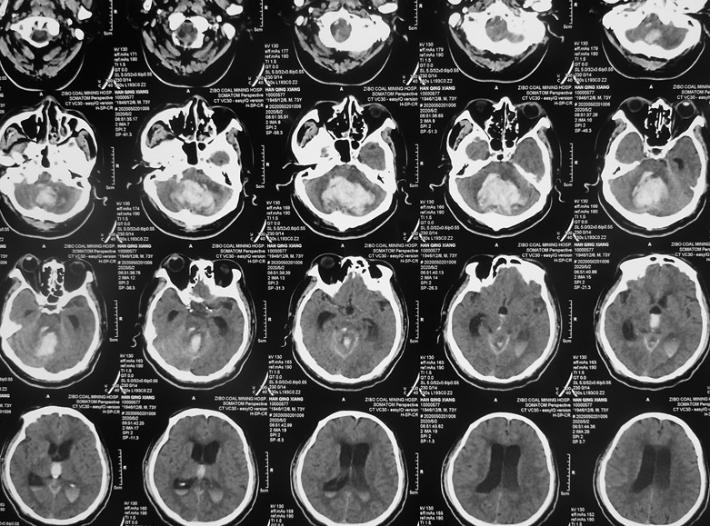

CT检查:小脑大量出血破入全脑室并梗阻性脑积水,脑干受压。

1周CT复查:脑室内积血有所吸收,但脑积水明显存在。患者昏迷状,瞳孔无明显变化。

半月CT复查:血肿明显吸收,脑积水有所改善。患者刺激可睁眼。

1月CT复查:血肿大部分吸收,脑积水缓解。患者可自行睁眼,有微弱意识反应,肢体肌力可达2到3级。